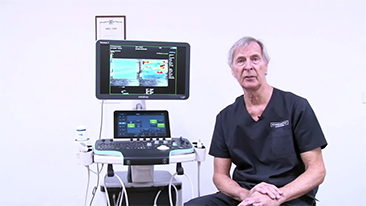

Unsere L?sungen zur Bildgebung orientieren sich am Bedarf der ?rzte und des Pflegepersonals, sowie am Wohl der Patienten. Wir verfolgen damit das Ziel, genauere Diagnosen und eine zuverl?ssige Behandlung in verschiedensten medizinischen Bereichen zu erm?glichen.